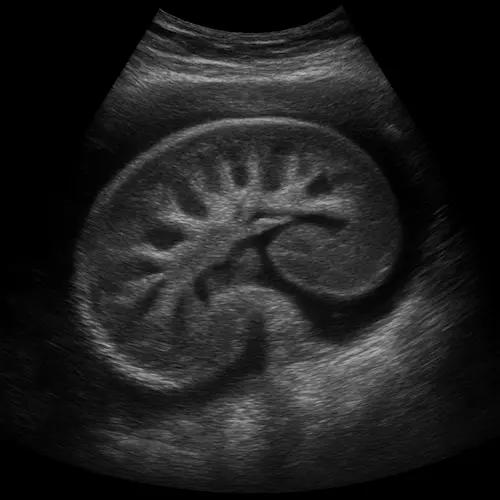

Diagnostics

“At the heart of Dr. SriNayan Katari’s practice is a commitment to diagnostic accuracy using evidence-based medical protocols. Leveraging his specialized training at institutes like JIPMER and Apollo, he employs a multimodal diagnostic approach to evaluate renal function and systemic health. This includes the precise interpretation of biochemical markers—such as the Glomerular Filtration Rate (eGFR), Serum Creatinine, and the Urine Albumin-to-Creatinine Ratio (uACR)—to accurately stage Chronic Kidney Disease (CKD). Furthermore, his expertise in Hypertension management allows for advanced hemodynamic monitoring to determine how blood pressure volatility is impacting renal vasculature. By correlating laboratory data with real-time clinical observations, he ensures that every patient receives a diagnosis that is both scientifically rigorous and deeply personalized.”

Nephrology

Management of Acute & Chronic Kidney Disease, Glomerular diseases, and Kidney Stones.